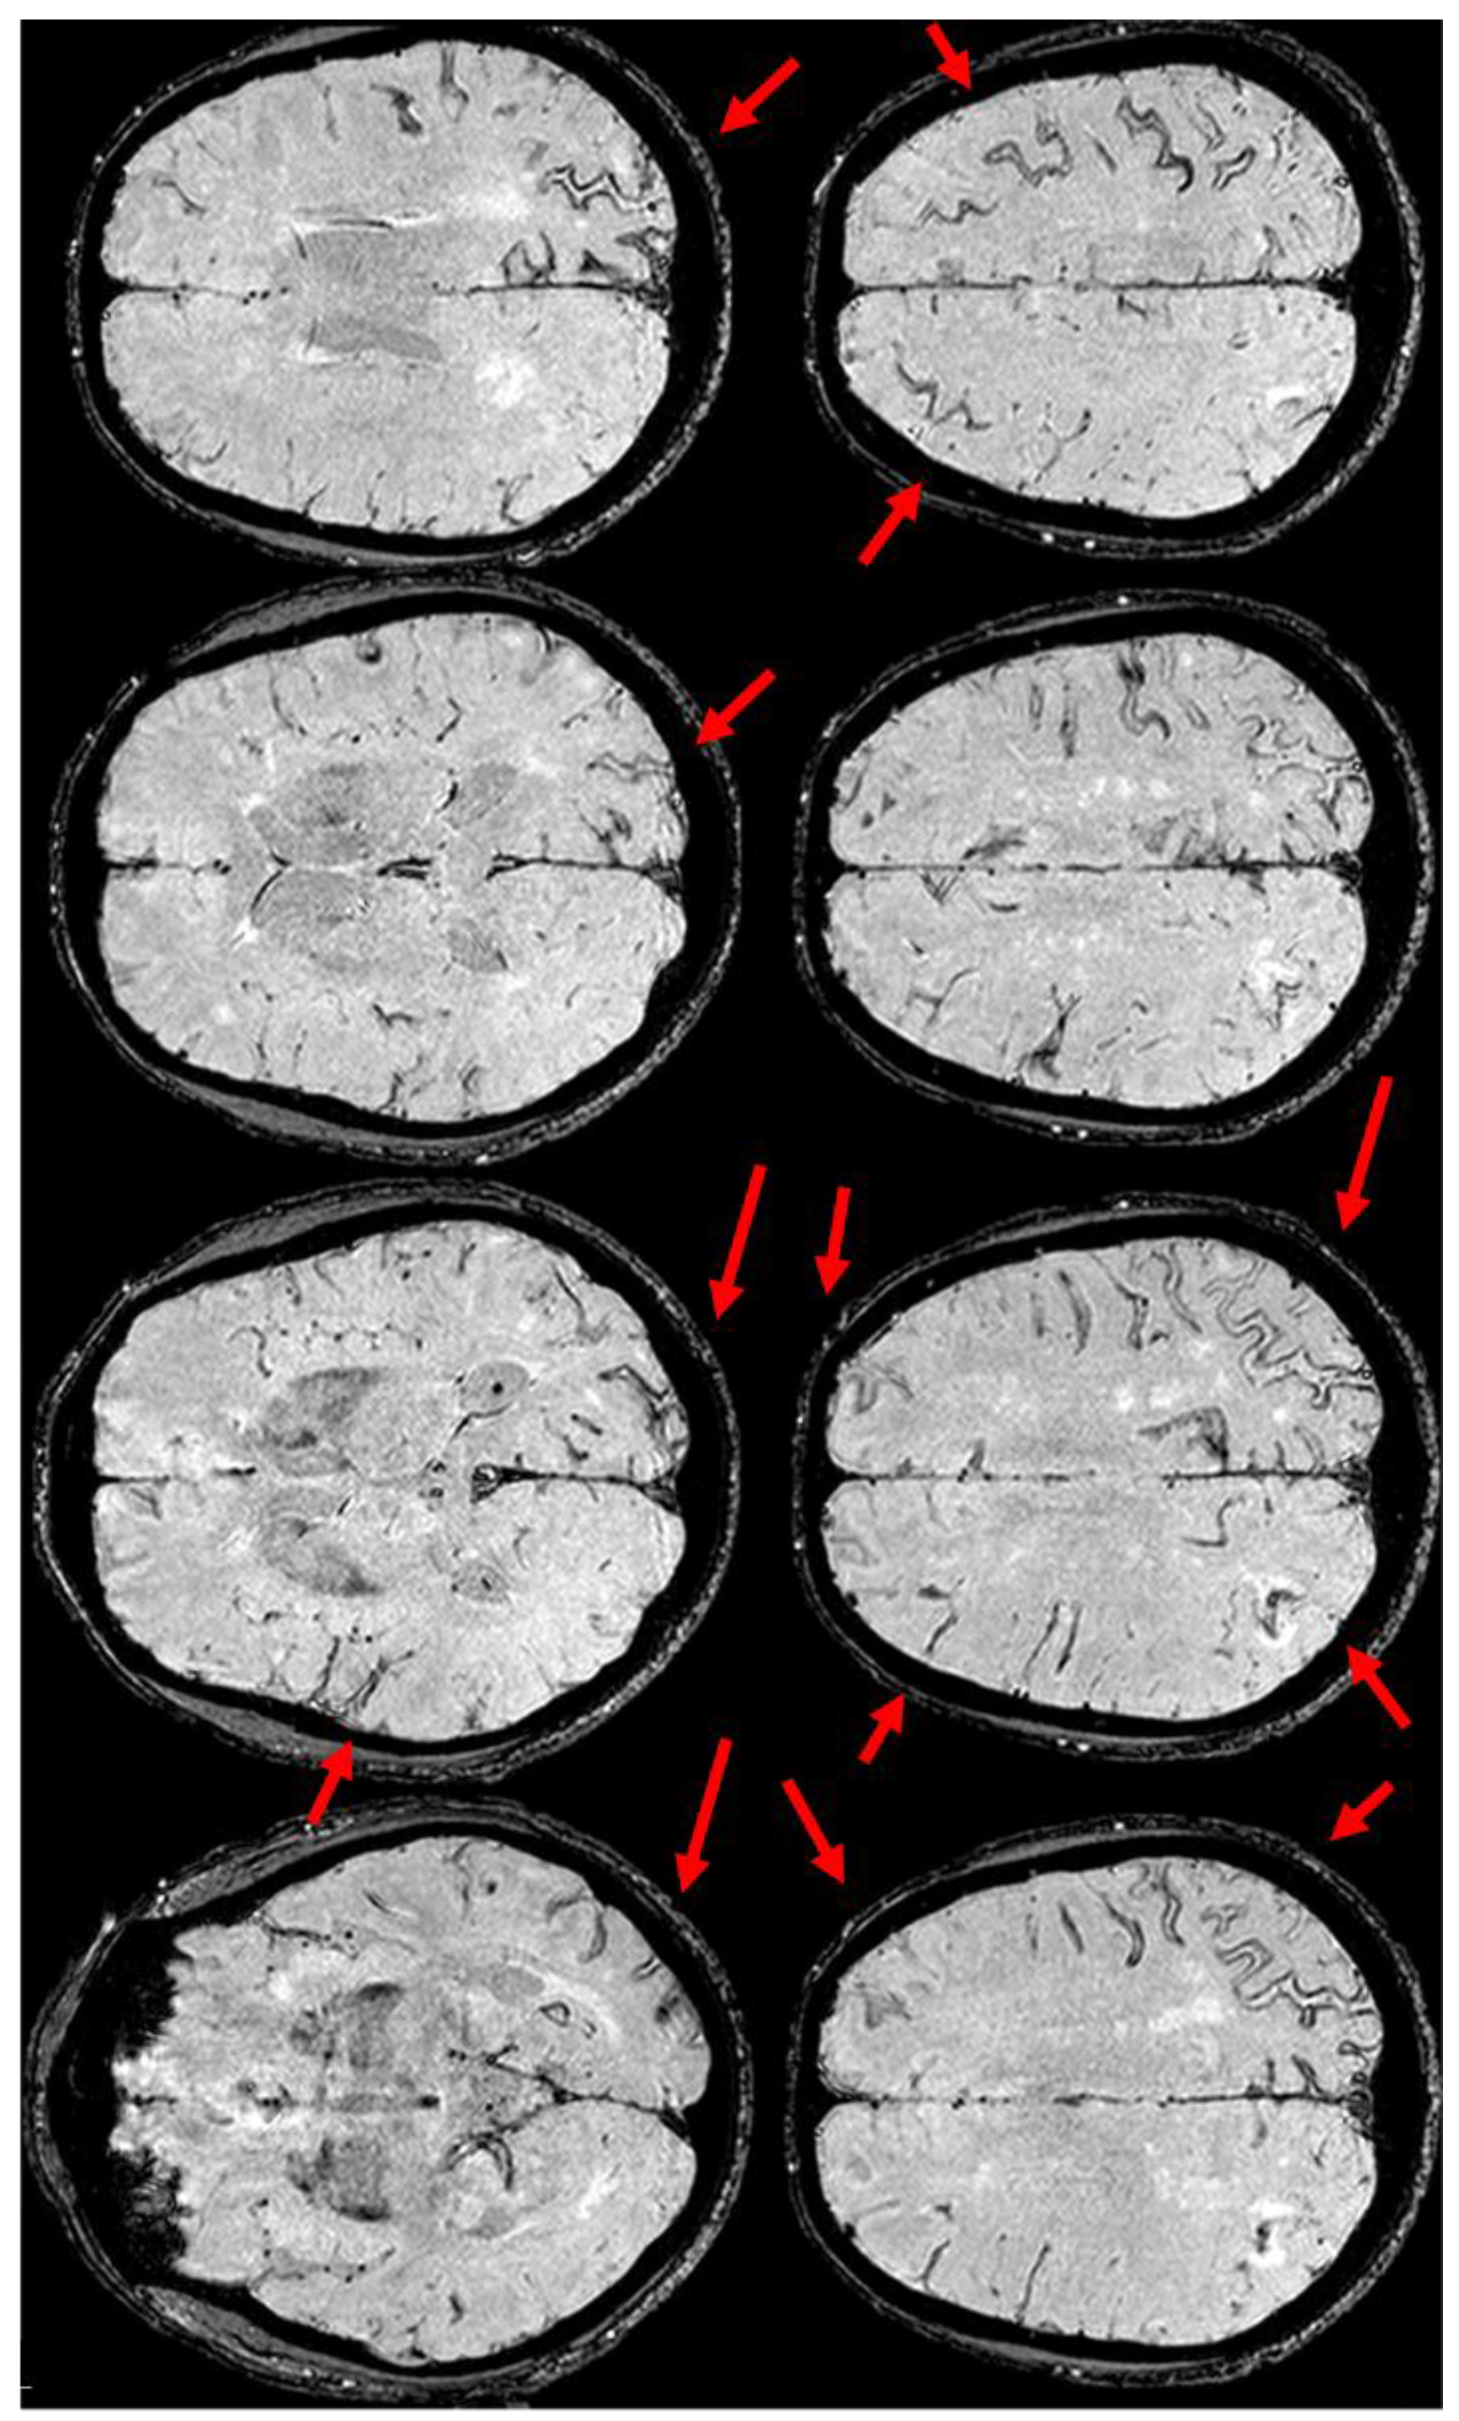

6. December 2017: Recurrent SAH

7. April 2018: Second Recurrent CAA-Related Inflammation